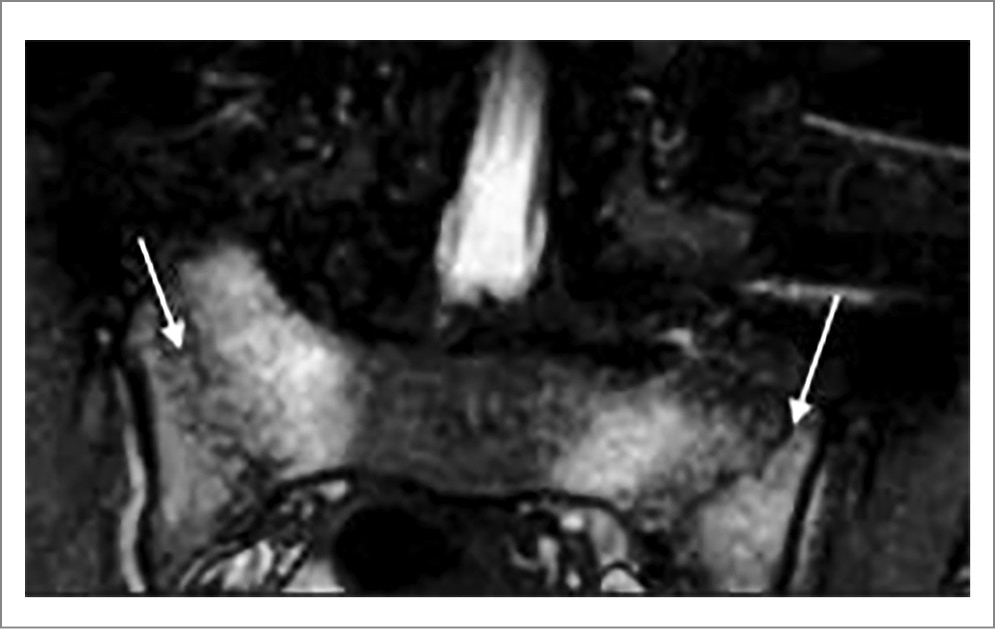

Иллюстрации типичного сакроилиита у пациентов с АС приведены на рис. 3 и 4.

Рис. 3. Пациентка Б. 22 лет, диагноз АС, длительность болезни 36 мес. КТ крестцово-подвздошных сочленений (коронарная проекция): широкий субхондральный склероз в подвздошных костях, справа мелкие эрозии в верхней части и участки расширения щели в нижней части сустава, слева множественные эрозии и участки расширения щели (двусторонний определенный сакроилиит).